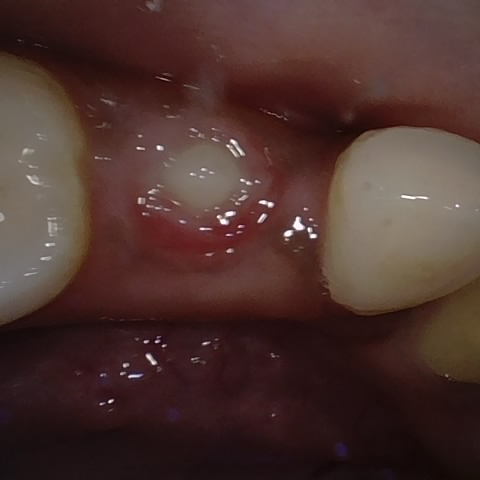

Annotated as "Good"